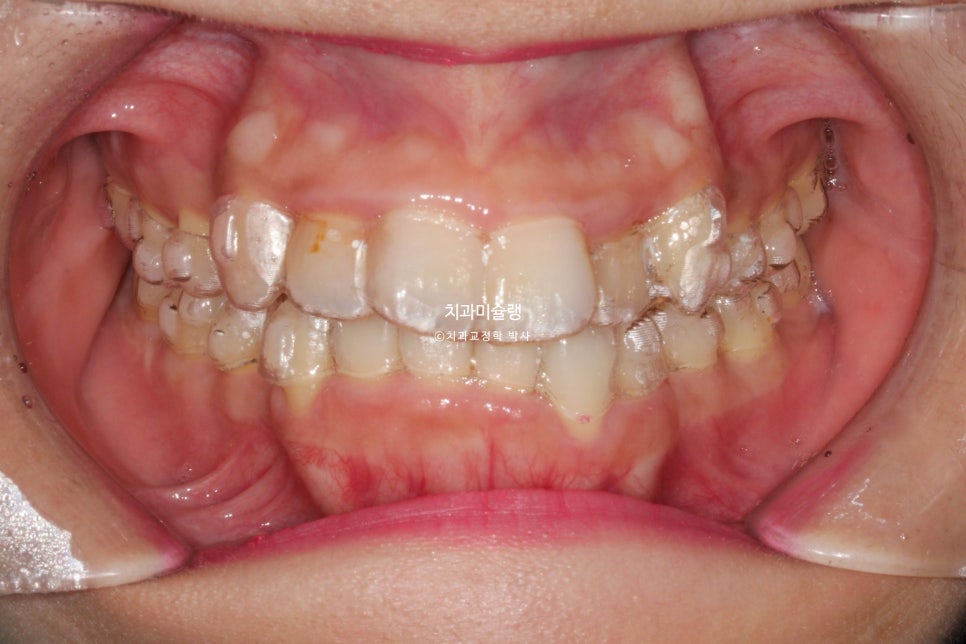

2025년 6월부터 2026년 1월까지, 30개의 추가장치를 모두 낀후 교합입니다.

발치공간, 덧니배열 등의 목표는 달성했지만 어금니 교합이 약간 뜹니다.

계획대로 치료가 잘 되어도 마지막 장치를 낀 직후에 이런상태가 되는 경우가 많아서 “인비절라인 치료하면 교합이 뜬다” 라는 오해를 많이 받습니다.

그러나 이상태에서 어금니 교합이 뜬 부분 때문에 재제작을 들어갈 필요는 없습니다.

장치 두께만큼 씹하는 부분이 환자의 교합력에 의해 뜨는거라, 장치 착용시간을 기존 22시간에서 잘때만 끼도록 하면 회귀 현상에 의해 어금니가 자연스럽게 닿게되며 교합이 안정화 됩니다.

어금니 교합이 뜨는 양, 환자의 교합력, 장치 끼는 패턴에 따라 주치의가 판단해야 하는 부분입니다.